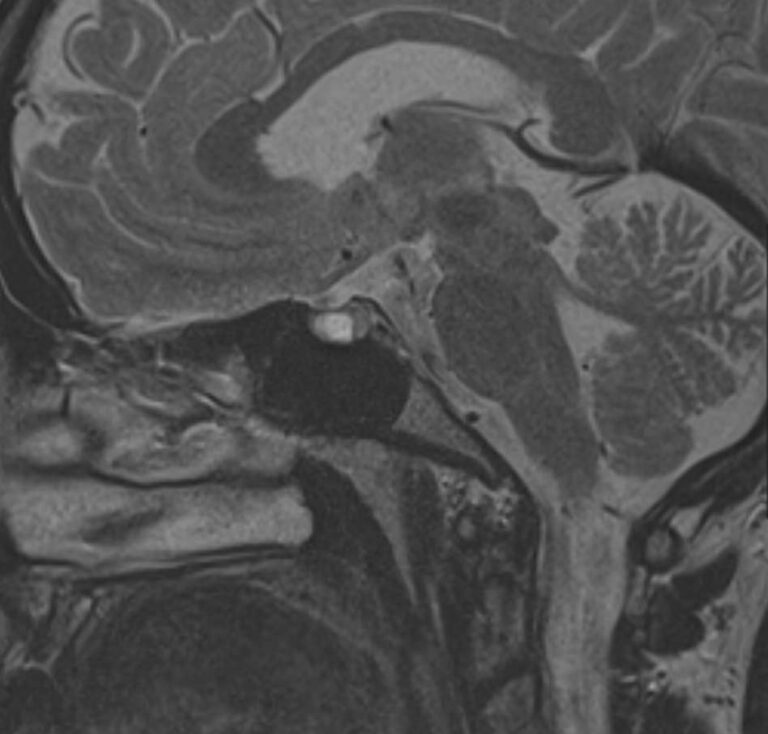

МРТ головного мозга позволяет оценить состояние всех структур головного мозга, однако для выявления патологии гипофиза назначается дополнительно МРТ гипофиза с прицельным осмотром области турецкого седла. Это два разных обследования, каждое из которых имеет свой протокол сканирования. Причем в подавляющем большинстве случаев МРТ гипофиза проводится с контрастным усилением, так как без этого данное исследование малоинформативно.

Опухоли гипофиза являются достаточно часто встречающейся патологией, особенно у людей молодого и среднего возраста. При этом выявляются как злокачественные, так и доброкачественные новообразования. В большинстве случаев обнаруживаются аденомы гипофиза (доброкачественные образования). При проведении стандартной МРТ головного мозга можно выявить достаточно большие опухоли гипофиза (от 1 см), а для выявления опухолевых образований меньших размеров (микроаденом) требуется МРТ гипофиза с контрастным усилением.

Гипофиз представляет собой округлую железу, находящуюся в основании головного мозга (на его нижней поверхности), расположенную в особой костной выемке, которая называется турецкое седло. Гипофиз тесно взаимодействует с гипоталамусом (это особая часть мозга), образуя гипоталамо-гипофизарную систему, которая влияет на работу остальных желез внутренней секреции, поэтому гипофиз считается центральным органом эндокринной системы. Гормоны гипофиза влияют на рост организма в целом, регулируют работу надпочечников, щитовидной железы, половых желез. Нормальное функционирование гипофиза определяет своевременность полового созревания подростков, отвечает за репродуктивную функцию человека, регулирует лактацию и родовую деятельность у женщин.

Метод позволяет создавать детализированные изображения всех структур головного мозга, в том числе области турецкого седла, и по праву считается лучшим способом диагностики любых объемных образований гипофиза. С помощью МРТ головного мозга и гипофиза можно выявить макроаденомы и большинство микроаденом (размером до 3мм).